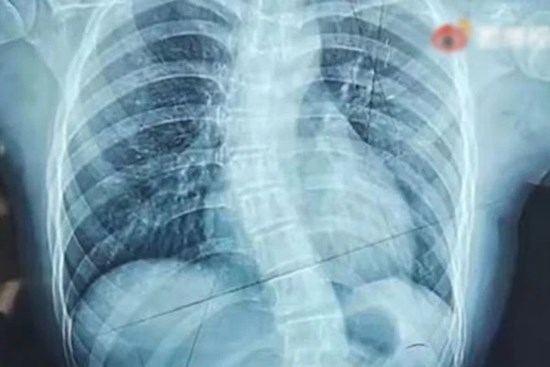

Nữ sinh 15 tuổi nhập viện vì đau lưng, cột sống biến dạng thành chữ S, tay dài tay ngắn, chân không bằng nhau chỉ vì 1 thứ rất nhiều người trẻ thường đeo trên lưng

Ngồi sai tư thế hoặc thường xuyên mang vác vật nặng, đeo túi lệch về 1 bên đều có thể gây cong vẹo cột sống nghiêm trọng.

Trẻ em hiện nay, việc áp lực học tập lớn, ngồi học trong thời gian dài, cũng có nguy cơ gây ra các bệnh nguy hiểm, tiêu biểu là bệnh vẹo cột sống như trường hợp của cô gái Tiểu Văn (TQ) trong cậu chuyện dưới đây.